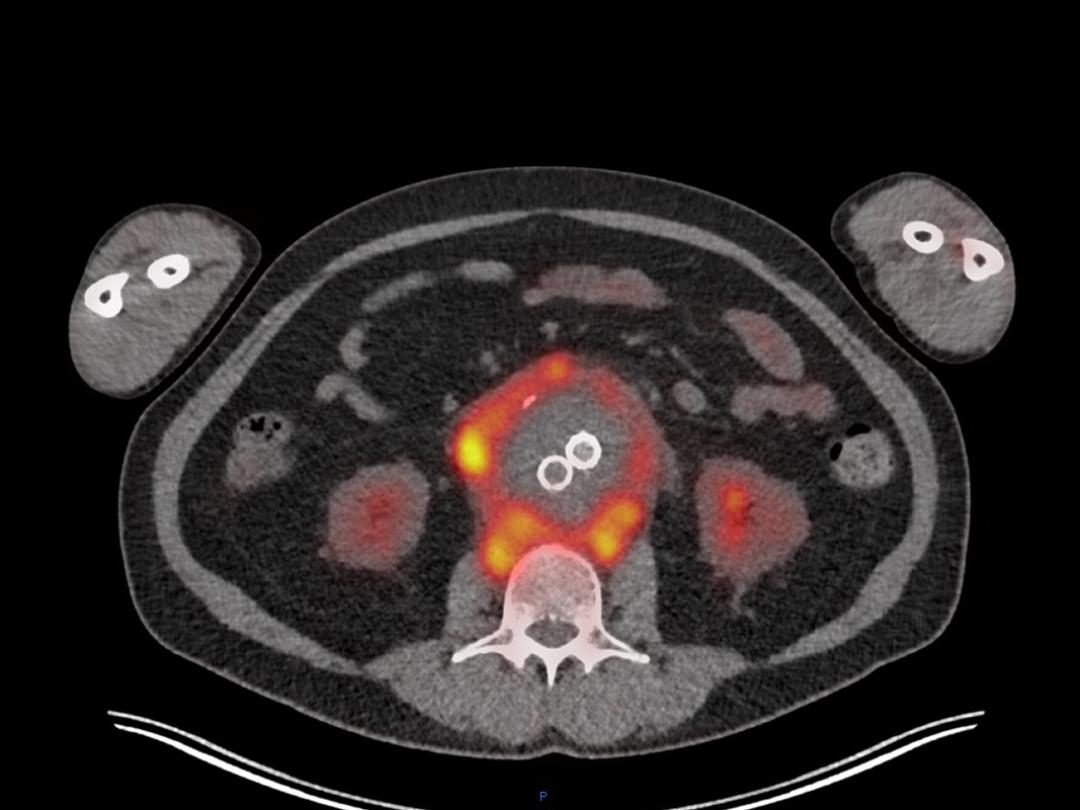

Een 65-jarige vrouw bekend met een abdominaal aorta-aneurysma kwam bij de huisarts vanwege malaise, gewichtsverlies (2 kg in 14 dagen) en sinds twee dagen progressieve rugpijn. Er volgde nadere analyse in het ziekenhuis. CT-angiografie van het abdomen liet vetinfiltratie zien rondom het aneurysma, wat werd geduid als lekkage. Omdat het aneurysma plotseling fors in diameter was toegenomen onderging de patiënte met spoed een endovasculaire operatie (‘endovascular aneurysm repair’; EVAR). Enkele weken postoperatief waren de klachten onveranderd en ontwikkelde de patiënte een subfebriele temperatuur; de ontstekingsparameters waren licht verhoogd. 18FDG-PET-CT-beelden lieten een sterk verhoogde metabole activiteit zien rond de aorta…